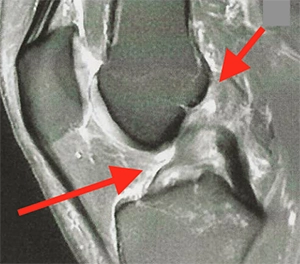

Une rupture du LCA

Comprendre les conséquences, l’instabilité et les options avant d’opérer.

Rupture du LCA : faut-il opérer ?